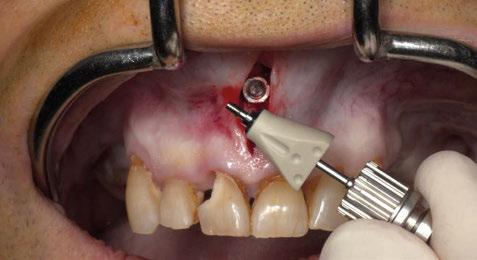

Figura 3. Intervención quirúrgica del caso clínico 1. a) situación clínica basal; b) colgajo de acceso apical vestibular y medición del defecto; c) posicionamiento ideal del injerto de tejido conectivo autólogo; d) sutura del injerto de tejido conectivo autólogo al colgajo a través del acceso apical vestibular.

Figura 4. Intervención quirúrgica del caso clínico 1. a) posición del injerto suturado a través del colgajo de acceso apical vestibular; b) utilización de aloinjerto particulado (OraGRAFT® Aloinjerto Cortical Particulado MIX 70% Mineralizado / 30% Desmineralizado) para rellenar el interior del defecto y cubrir la dehiscencia ósea; c) cobertura de la dehiscencia ósea con el aloinjerto particulado; d) customización de la lámina de cortical acorde a las características del defecto (Lámina de cortical desmineralizada Cortiflex® Salugraft Dental).

Una vez preparado el lecho receptor, dada la existencia de una situación combinada de recesión gingival y una dehiscencia ósea vestibular con pérdida de inserción interproximal, se opta por la utilización combinada de un injerto de tejido conectivo autólogo tuberositario, un sustituto de origen alogénico (Lámina de cortical desmineralizada Cortiflex® Salugraft Dental) que se fija mediante dos chinchetas a ambos lados, cubriendo un injerto óseo de origen alogénico particulado (OraGRAFT® Aloinjerto Cortical Particulado MIX 70% Mineralizado / 30% Desmineralizado). Primero se suturó el injerto de tejido conectivo autólogo al colgajo, después se colocaron las partículas